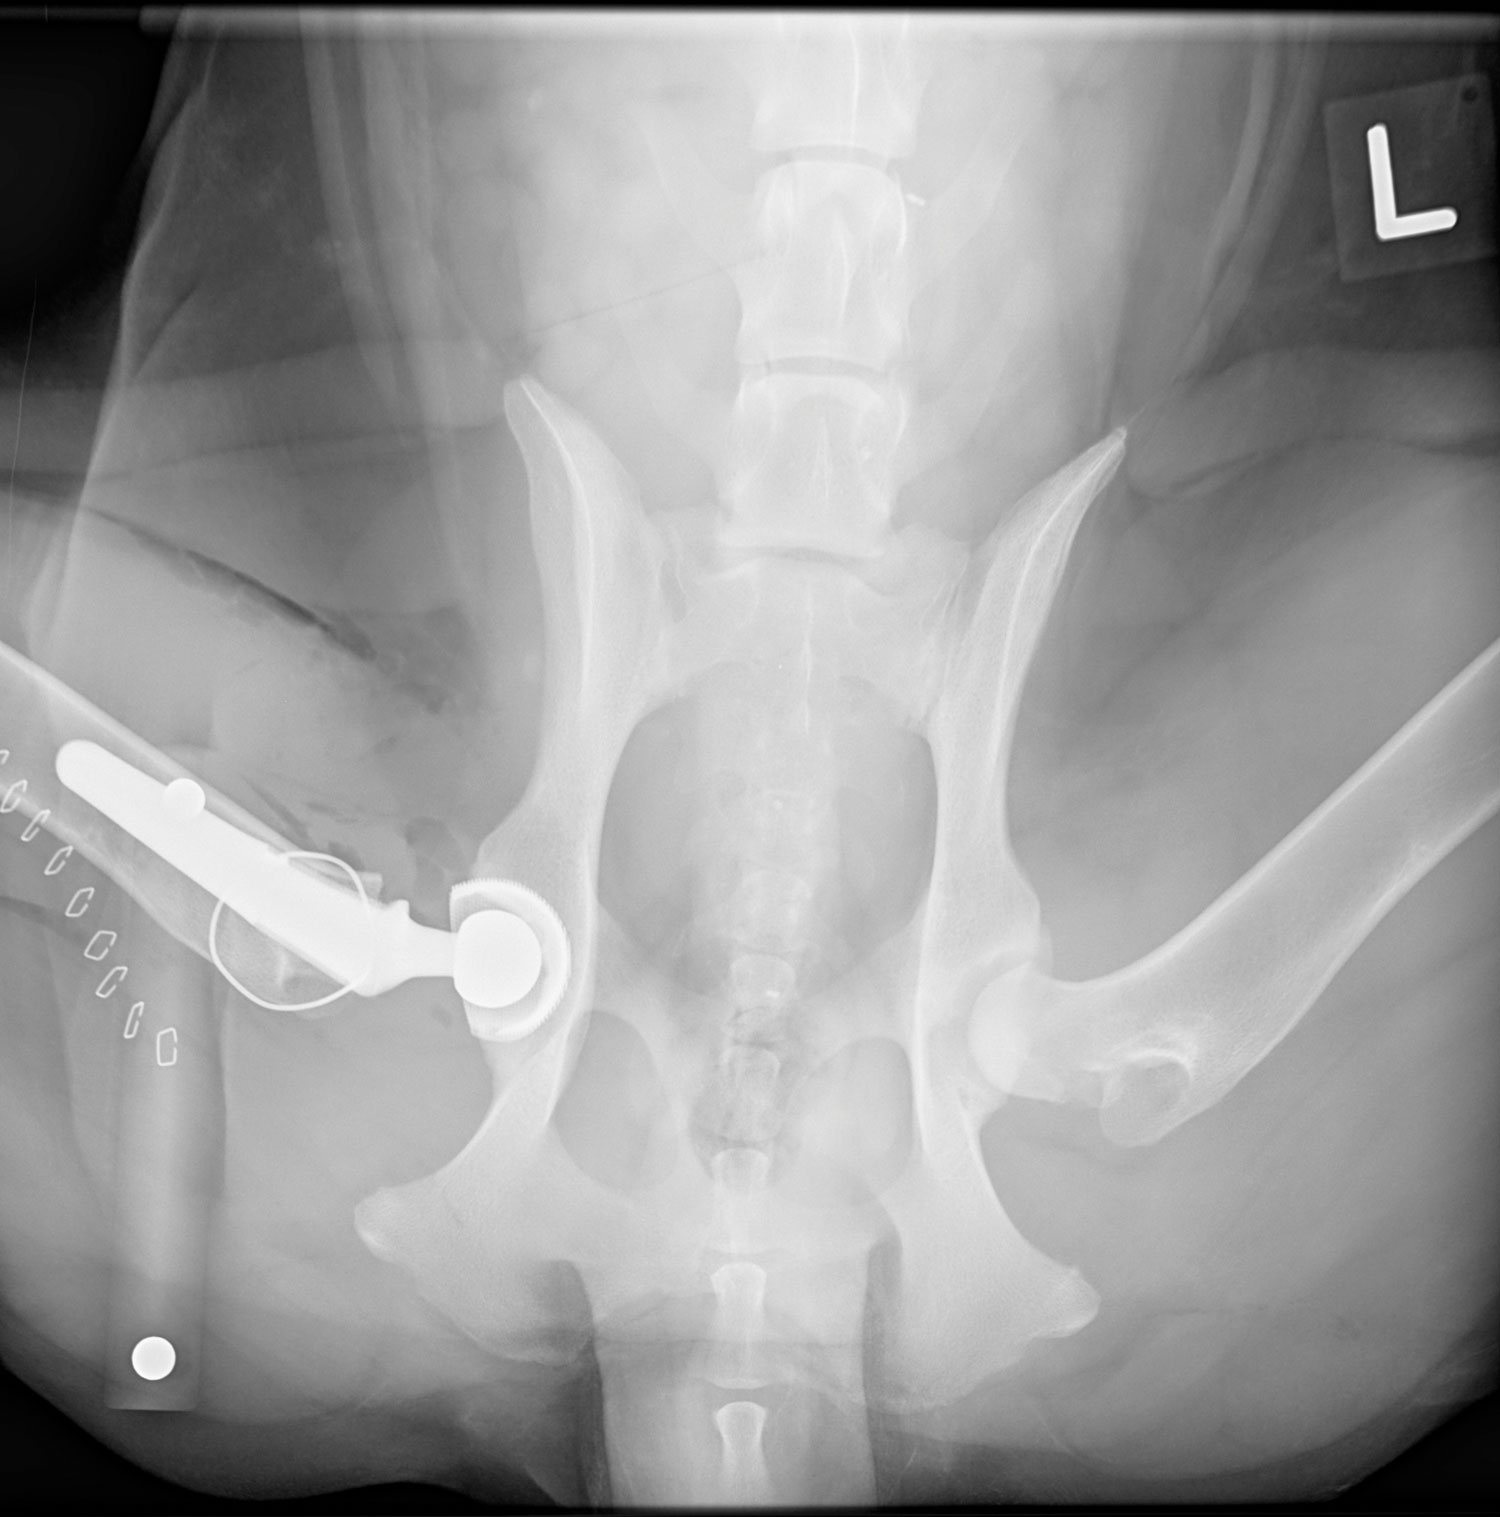

Primary care veterinarian, Craig Lamarsh, DVM, of Southern Animal Foundation, examined Fiona and diagnosed her with hip dysplasia, a condition that occurs during the growth stage in dogs and involves the loosening of the hip joint, causing dysfunction and pain. He recommended total hip replacement surgery. Charles M. Walls, DVM, DACVS, professor of small animal surgery, performed a right-sided total hip replacement surgery in May 2021 at LSU Vet Med. Fiona was 11 months old.